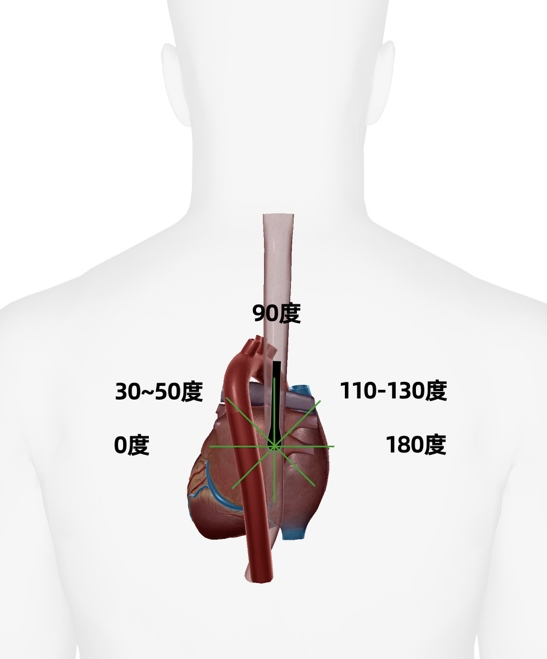

根据二尖瓣的解剖分区,前叶分为 A1、A2 及 A3 部分,相对应的后叶也分为 P1、P2、P3 部分(图 10)。1 区位于前外侧、3 区位于后内侧。该探查切面所经过的二尖瓣 P3、A2、P1 等部分形成一个经典的「波浪」图像(图 11)。此切面是二尖瓣缘对缘修复术(TEER)中的重要参考依据,也可以用于评估左心室功能、左心房病变等。

从心房向心室方向观察,蓝线为 commissural view 超声切面大致方向

图 11:TEE 图像(commissural view,动图)